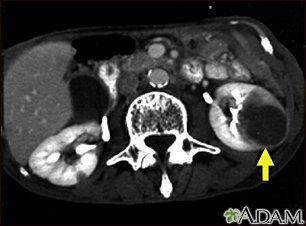

Kidney metastases - CT scanBackKidney metastases - CT scanA CT scan of the middle abdomen showing metastasis (cancer that has spread) in the left kidney in a patient with carcinoma of the lung. Note the large dark circular tumor in the kidney on the right side of the picture. E-mail FormEmail ResultsName:Email address:Recipients Name:Recipients address:Message: